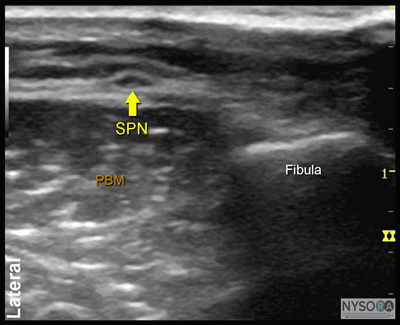

Figure 7:Transducer position and needle insertion to block the superficial peroneal nerve. ![]() Figure 8: Cross-sectional anatomy of the superficial peroneal nerve (SPN). EDL, extensor digitorum longus muscle; PBM, peroneus brevis muscle. Superficial Peroneal Nerve The superficial peroneal nerve innervates the dorsum of the foot. It emerges to lie superficial to the fascia 10 to 20 cm above the ankle joint on the anterolateral surface of the leg. A transducer placed transversely on the leg, approximately 5 cm proximal and anterior to the lateral malleolus, will identify the hyperechoic nerve lying in the subcutaneous tissue immediately superficial to the fascia (Figures 7, 8, and 9A and B). If the nerve is not readily apparent, the transducer can be traced proximally on the leg until, at the lateral aspect, the extensor digitorum longus and peroneus longus muscles can be seen with a prominent groove between them leading to the fibula (Figure 10A and B). The superficial peroneal nerve is located in this intermuscular septum, just deep to the fascia. Once it is identified at this more proximal location, it can be traced distally to the ankle. Because the superficial nerves are rather small, their identification with ultrasound is not always possible in a busy clinical environment. Sural Nerve The sural nerve innervates the lateral margin of the foot and ankle. Proximal to the lateral malleolus, the sural nerve can be visualized as a small hyperechoic structure that is intimately associated with the small saphenous vein (Figures 11, 12, and 13A, B). A calf tourniquet can be used to increase the size of the vein, aiding in identification of the nerve. Saphenous Nerve The saphenous nerve innervates the medial malleolus and a variable portion of the medial aspect of the leg below the knee. The nerve travels down the medial leg alongside the saphenous vein. Because it is a small nerve, it is best visualized 10-15 cm proximal to the medial malleolus, using the saphenous vein as a landmark (Figures 14, 15, and 16A, B). A proximal calf tourniquet can be used to assist in increasing the size of the vein. The nerve appears as a small hyperechoic structure.

Figure 9: (A) Ultrasound anatomy of the superficial peroneal nerve (SPN). (B) Ultrasound anatomy of the superficial peroneal nerve with structures labeled. PBM, peroneus brevis muscle.